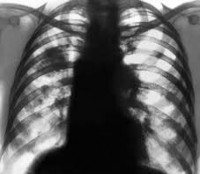

• Радиационная диагностика. Симптомы экзогенной липидной пневмонии появляются на КТ легких через 30 минут, на рентгенограммах - через 24 часа после контакта с патологическим фактором. Рентгенологически определены участки дренирования легочной инфильтрации, расположенные в средней и нижней долях правого легкого. Обнаружены КТ инфильтраты из матированного стекла низкой интенсивности или узелковые образования, расположенные в тех же областях.